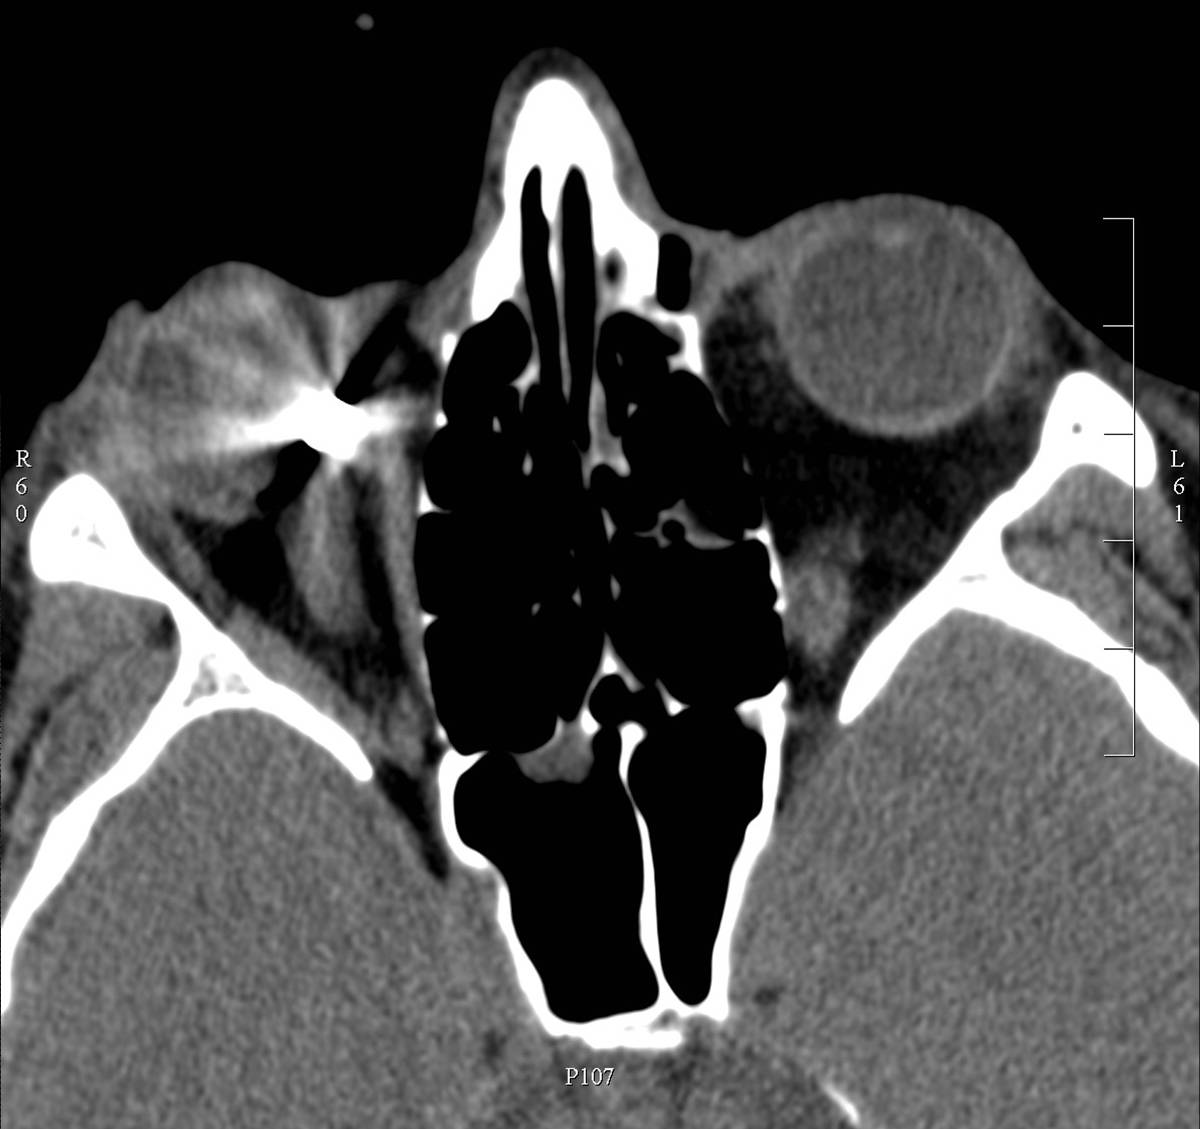

CT has an important role in the assessment of orbital bony injuries and localization of foreign bodies. In trauma the advantages of CT are its ability to visualize any region without summation, to provide tomographic image and to detect tiny bony fractures without dislocation. Radioopaque foreign bodies can be localized easily by CT; however, the localization of radiolucent foreign bodies can be assessed only by indirect signs, especially in perforating bulbar injury. Bony destructions can be assessed by CT in either primary or secondary orbital tumours.

2. image: Axial view of the orbits in noncontrast CT. Metallic foreign body (indication for CT) in the medial part of the right orbit.